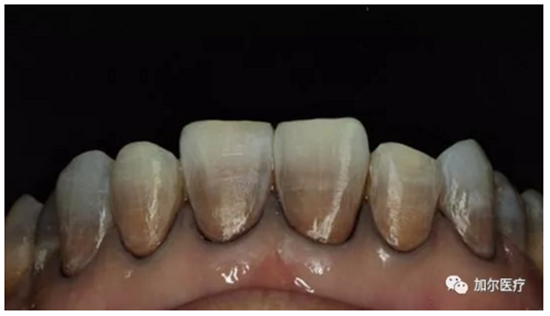

3.png

判斷牙齒是否還有知覺!

1、牙髓病死最大的感知就是牙齒沒有什么感覺,連吃飯冷熱酸甜一點反應(yīng)都沒有,另外還會經(jīng)常出血,一般深齲傷及牙髓剛開始是慢性牙髓炎。

2、到后來牙齒沒有了營養(yǎng)來源,咬過硬東西時牙冠一不小心就會崩壞。